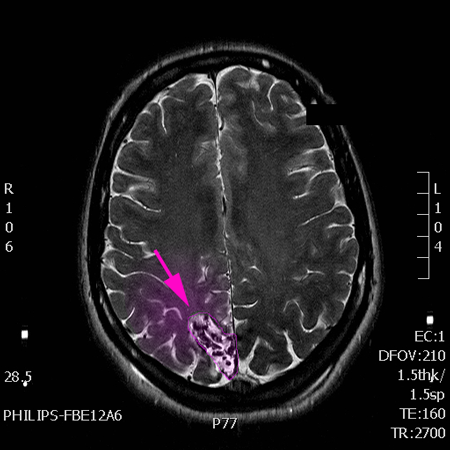

AVM3

Αρτηριοφλεβώδης δυσπλασία, μάζα παθολογικών αγγείων με χρώμα